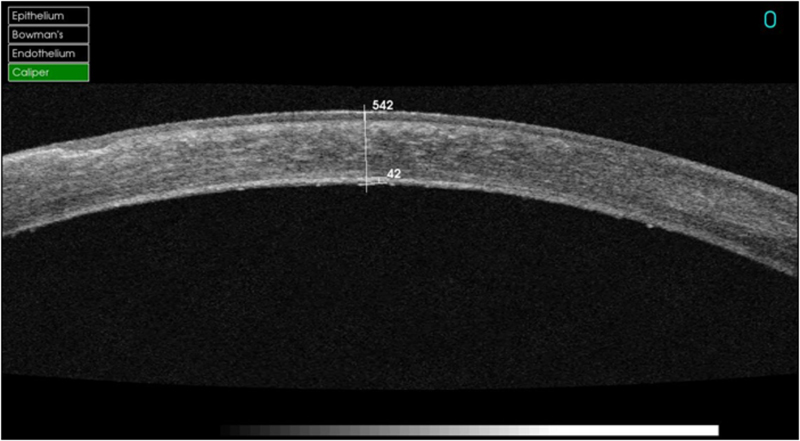

Podemos mostrar unos ejemplos para ver la utilidad de la OCT. En los casos de opacidades anteriores que no afectan al endotelio se realiza la técnica de DALK. La mayoría de pacientes están afectados por opacidades estromales infecciosas, como el virus del herpes simple (VHS), por distrofias corneales, y también por el queratocono. En la

Figura 6 podemos observar una técnica de DALK predescemética, en este caso observamos un lecho de estroma, MD y endotelio de 42 micras. Ésta técnica es de elección en casos donde se quiere evitar realizar una cirugía penetrante por los riesgos que comporta (por ejemplo el herpes corneal). En la siguiente foto podemos ver una DALK descemética realizada en una paciente con queratocono (

Figura 6. DALK predescemética.